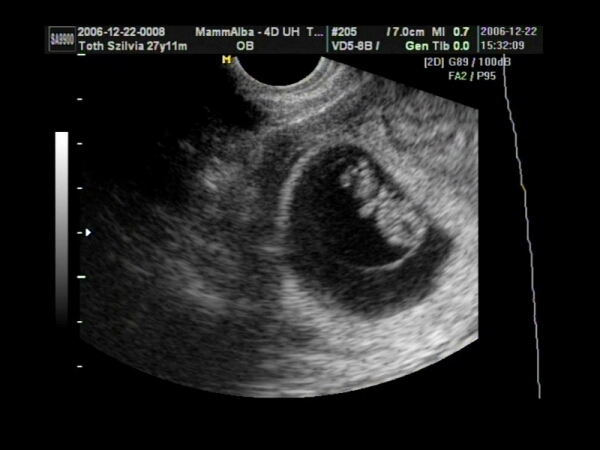

Magdolnam, kerestem neked UH fotókat. Ez egy 6 hetes magzat:

Kép

Ez pedig egy 9 hetes baba:

Remélem, tudtam segiteni!